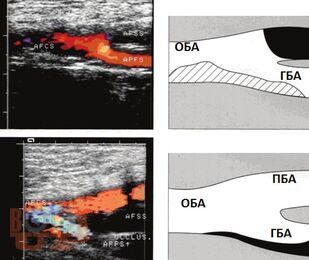

В учебном пособии раскрыты клинические особенности пациентов с окклюзирующими заболеваниями артерий нижних конечностей; представлены клинические и лабораторные методы исследования. Особое внимание уделено медицинской реабилитации пациентов после бедренно-подколенного шунтирования.